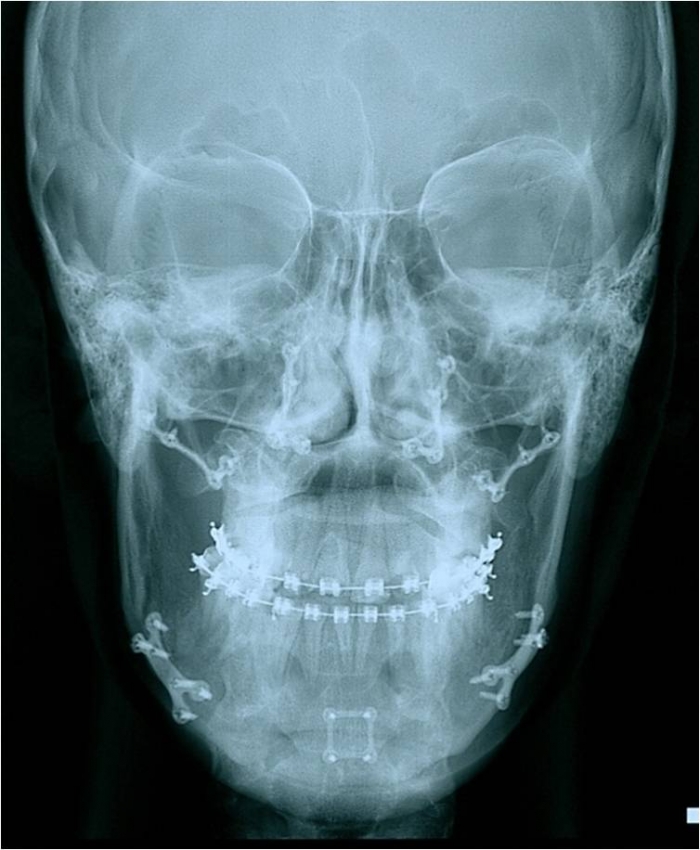

Telerradiografia frontal inicial - Clínica Cliniface

Telerradiografia frontal inicial